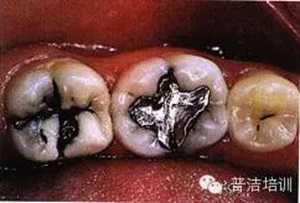

一、下頜后牙牙合面廣泛齲壞,檢查后決定行樹(shù)脂嵌體修復(fù)

二、去除齲壞的組織,可以使用送風(fēng)公司生產(chǎn)的齲齒檢測(cè)液來(lái)判斷齲壞的組織是否去除干凈